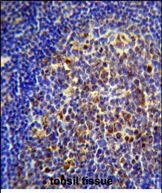

IHC 1/100-1/500 Human,Mouse,Rat

The CHRNA10 antibody targets the alpha 10 subunit of the nicotinic acetylcholine receptor (nAChR), a ligand-gated ion channel involved in synaptic signaling. Encoded by the *CHRNA10* gene, this subunit typically pairs with the alpha 9 subunit (CHRNA9) to form functional heteromeric receptors. CHRNA9/10 receptors are predominantly expressed in the inner ear’s cochlear hair cells, where they mediate efferent modulation of auditory signaling, influencing sound amplification and auditory processing. Beyond the auditory system, CHRNA10 has been detected in non-neuronal tissues, including immune cells, epithelial cells, and certain cancers, suggesting roles in inflammation, cell proliferation, and tumorigenesis.

Antibodies against CHRNA10 are critical tools for studying its expression, localization, and function. They are used in techniques like Western blotting, immunohistochemistry, and immunofluorescence to map receptor distribution in tissues or assess protein levels in disease models. Research using these antibodies has highlighted CHRNA10's potential involvement in hearing disorders, such as autosomal dominant hearing loss linked to *CHRNA10* mutations. Additionally, studies implicate CHRNA10 in cancer progression, with altered expression observed in lung, breast, and head-neck cancers, possibly influencing cell survival and metastasis.